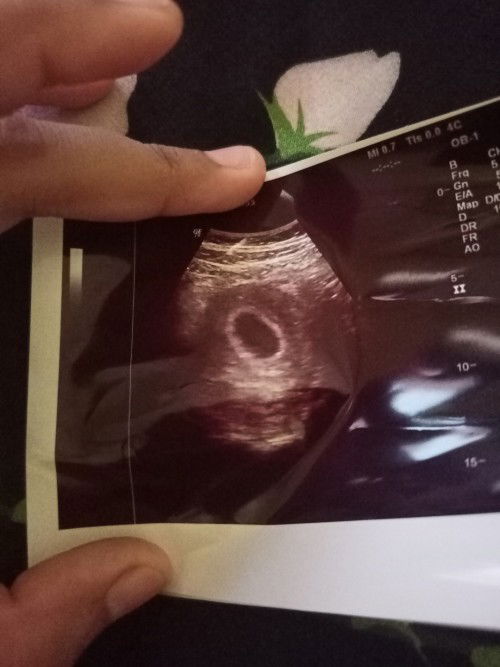

Sudah 9 minggu tapi janin belum kelihatan kenapa ya? Ada yg pernah mengalami bun?

bener kan ttep positif thinking ,, asam folat konsumsi tiap hari jangan lupa ,, banyak makan sayuran ,, insaallah Allah ngasih yg terbaik buat kk.. semoga pas 12 week bakal janin sudah kelihatan . amin ya Allah 🤲 pengalam pribadi saya yah kak . pas kehamilan kedua saya saya positif hamil hanya periksa ke bidan .. itupun saya tidak di kasih vitamin dan penguat kandungan kk . biasa aja intinya .. jdi pas usia kehamilan 10 week saya di sarankan untuk USG .. dan hasilnya B.O kk di nyatakan hamil kosong .. di suruh balik 2 Minggu kemudian . disaat blum kembali yah saya kluar flek dan di susul pendarahan hebat kk.. jdi saya akhirnya keguguran . dan setelah kuret selang 15 bulan Alhamdulillah sekarang di kasih kepercayaan lagi sama Allah 🤲. USG awal saya di usia kehamilan 7 week kk.. Alhamdulillah bakal janin dan djj nya sudah ada .. saya Bun terus konsumsi asam folat dr dokter.. ini USG saya pas awal kehamilan pake usg transVaginal kk.. jdi kehamilan di usia dini lebih baik langsung USG pake transVaginal .. soalnya terkadang kalau USG biasa memang Ndak kedetec kk .. seperti saya perutnya tebel . 🤭🤭 di coba USG biasa kelihatan kantongnya aja.. eh pas di coba pake transVaginal ada di ai bakal janin 🤲🥰❤️❤️

Baca lagiitu masih wajar bun, mungkin baru kantungnya saja. aku waktu hamil kemarin usg pertama kali ya usianya baru 6w5d jd baru kantungnya saja, itu jga harus nahan pipis dari jam 6 pagi smpai jam 10. jd usahakan perbanyak istirahat aja bun, jngn capek2 jngn motoran, jgn angkat beban berat dlu trs utamanya obat penguat kandungan d minum. memang kehamilan tiap orang beda2, tp jaga2 aja, aplgi trimester pertama.

Baca lagiPengalaman aku kemarin pas 8mingguan bun, dokter bilang belum kelihatan cuma ada kantungnya aja tapi aku bilang, coba dizoom lagi dok. Pas dizoom baru deh kelihatan janinnya wlpn masih kecil banget & pas dicek udah ada djj nya 😅 soalnya pas dokternya bilang masih kantung, didlm kantungnya aku lihat kayak ada bulatan samar bgt 😁

nnti usg lagi yaa bund 4 mgg kmudian insyaallah sdh kliatan calon bakal janinnya ... d awal kehamilan mmg msh terlihat kantong janin it hal normal ya bund ... ttp positif thinking jgn kpikiran perkataan org .. Krn kesehatan ibu hamil berbeda beda d stiap org ... sehat sllu bund

wajar Bun....itu karna memang masih sangat kecil...tp pas pertama sy lakuin USG transvaginal langsung karna lebih bagus si kata dokternya biar tau calon Dede nya ..sya mlh USG usia 8minggu Bun...pake USG transvaginal dan ternyata memang ada...coba sabar dulu nanti coba USG lagi Bun usia 4bulan